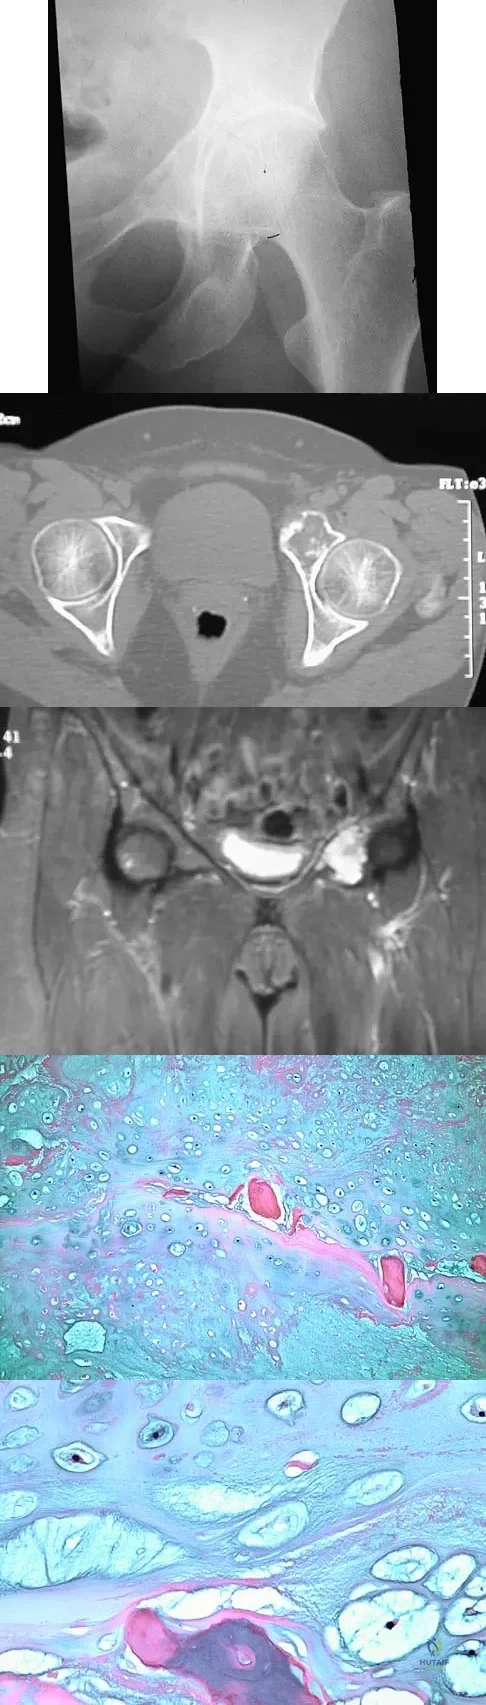

A 43-year-old woman has had pain in the left hip for the past 2 months. A radiograph, CT scan, MRI scan, and biopsy specimens are shown in Figures 16a through 16e. What is the most likely diagnosis?

Explanation